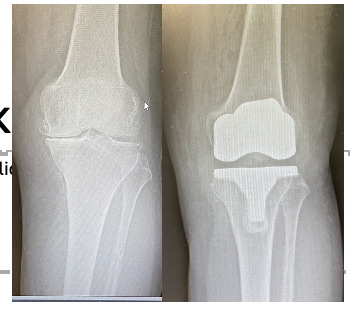

Implant Choices

Modern implants are typically:

• Cobalt-chromium alloy with polyethylene insert

• Cemented fixation in most cases

• Occasionally cementless in selected patients

Most contemporary implants are highly reliable. It may be useful to ask if your implant is ODEP10A rated. This means that it has a good track record for over ten years in the majority of patients. But….

There is a paradox, in that newer implants with modern technology will not have this rating. But remember, newer does not always mean better, and with a shorter track record these implants are not fully proven in the long term.